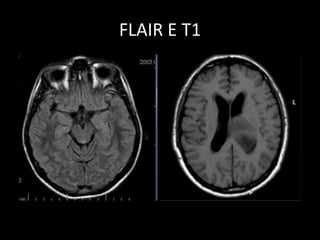

• Utilizada em exames de crânio.

• T2, mas o líquido fica preto (sem

sinal)-TI longo.

• Utiliza um pulso de inversão pra

saturar o sinal do LCR.

FLAIR

• Imagens de lesão no parênquima

cerebral serão evidenciadas no

FLAIR.

• Sequência mais importante no

estudo do encéfalo.

FLAIR E T2

FLAIR E T1

• Utilizada emexames de crânio. • T2, mas o líquido fica preto (sem sinal)-TI longo. • Utiliza um pulso de inversão pra saturar o sinal do LCR. FLAIR

• 45.

• Imagens delesão no parênquima cerebral serão evidenciadas no FLAIR. • Sequência mais importante no estudo do encéfalo. FLAIR